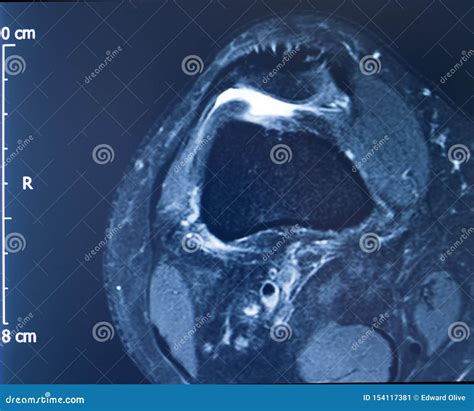

An Mcl Tear Mri is a non-invasive imaging technique that provides detailed images of the knee joint. MRI uses magnetic fields and radio waves to create cross-sectional images of the body’s internal structures. This allows healthcare professionals to visualize the MCL and other soft tissues in the knee, identifying any tears or damage.

During an *Mcl Tear Mri*, the patient lies on a table that slides into a large, cylindrical machine. The procedure is painless and typically takes about 30-60 minutes. The MRI machine captures multiple images from different angles, providing a comprehensive view of the knee joint.

An *Mcl Tear Mri* is particularly useful for differentiating between an MCL tear and other knee injuries, such as meniscal tears or anterior cruciate ligament (ACL) injuries. This information is crucial for developing an appropriate treatment plan.